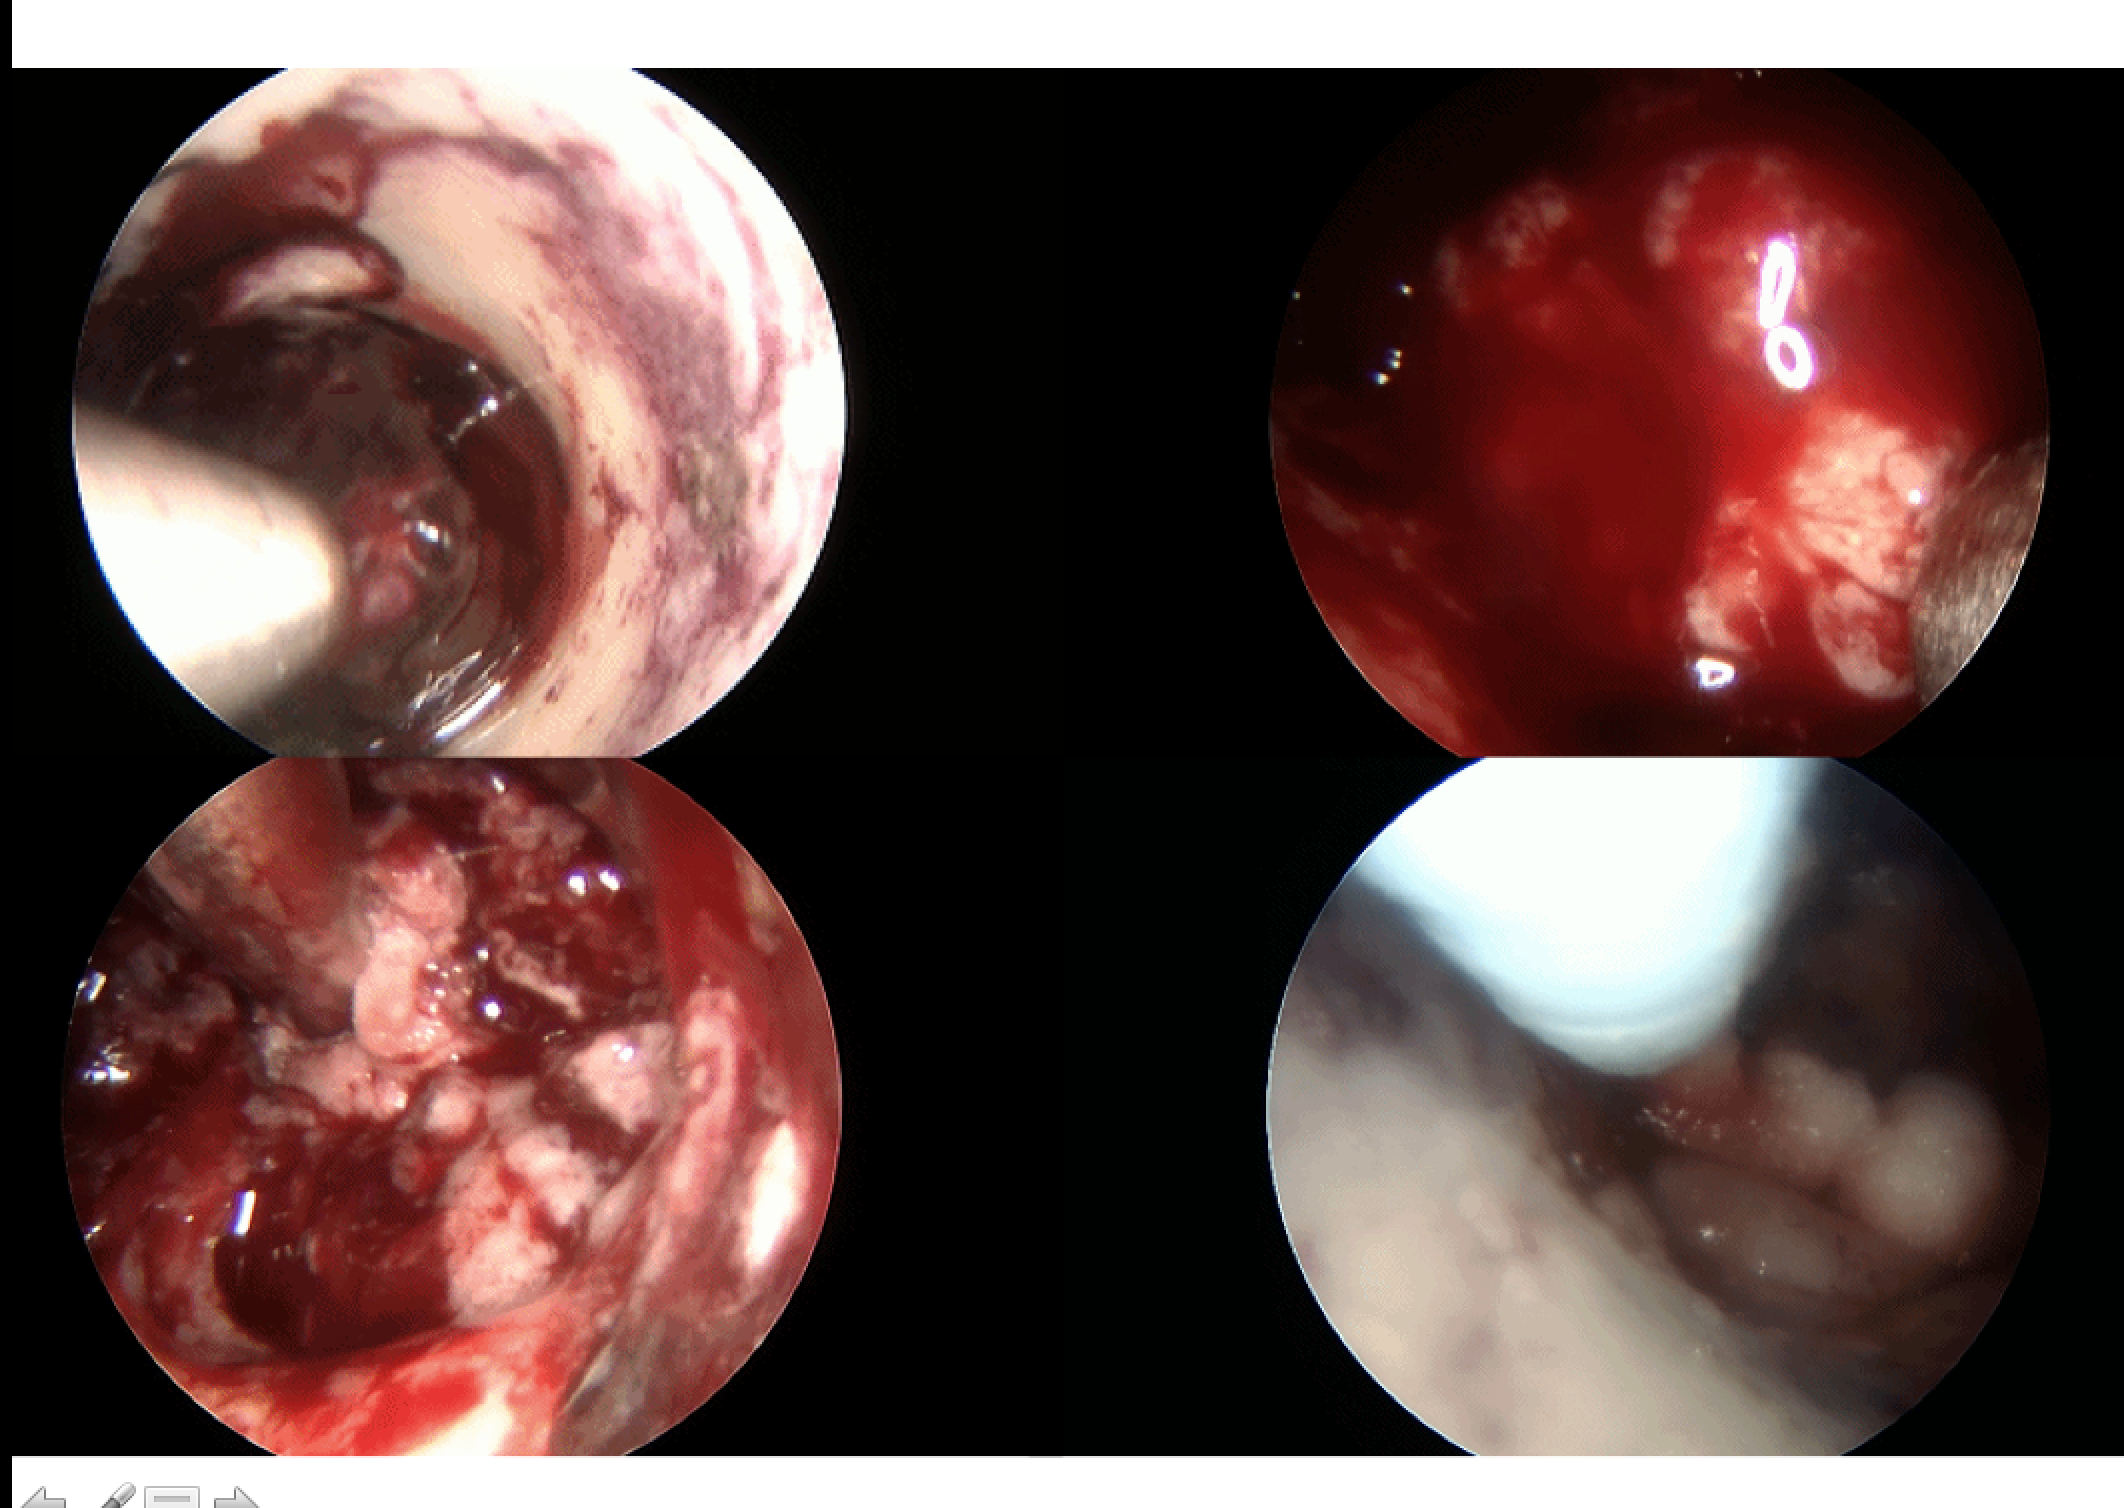

内镜下清除脑内及脑室血肿

神经内镜微创治疗高血压脑出血